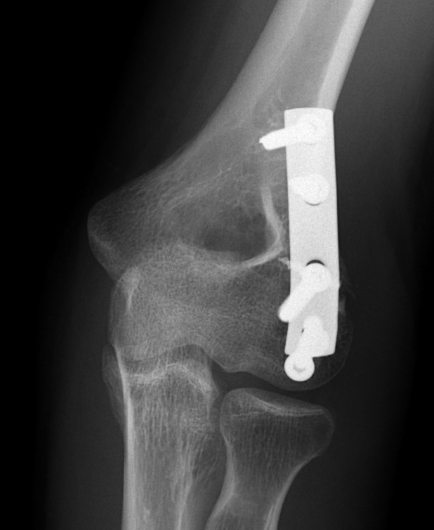

Fixation

Headless compression screws AP / PA

Usually AP headless compression screws (violates articular surface)

- +/- PA screws (risk AVN)

AP v PA screws

Heller et al J Hand Surg Am 2025

- systematic review of AP v PA screws capitellum fixation

- higher AVN with PA screws (29% vs 11%)

- higher revision fixation with AP screws (7 v 3%)

- higher heterotopic ossification with AP screws (22 v 7%)

ORIF with AP screws

ORIF Type II with screws